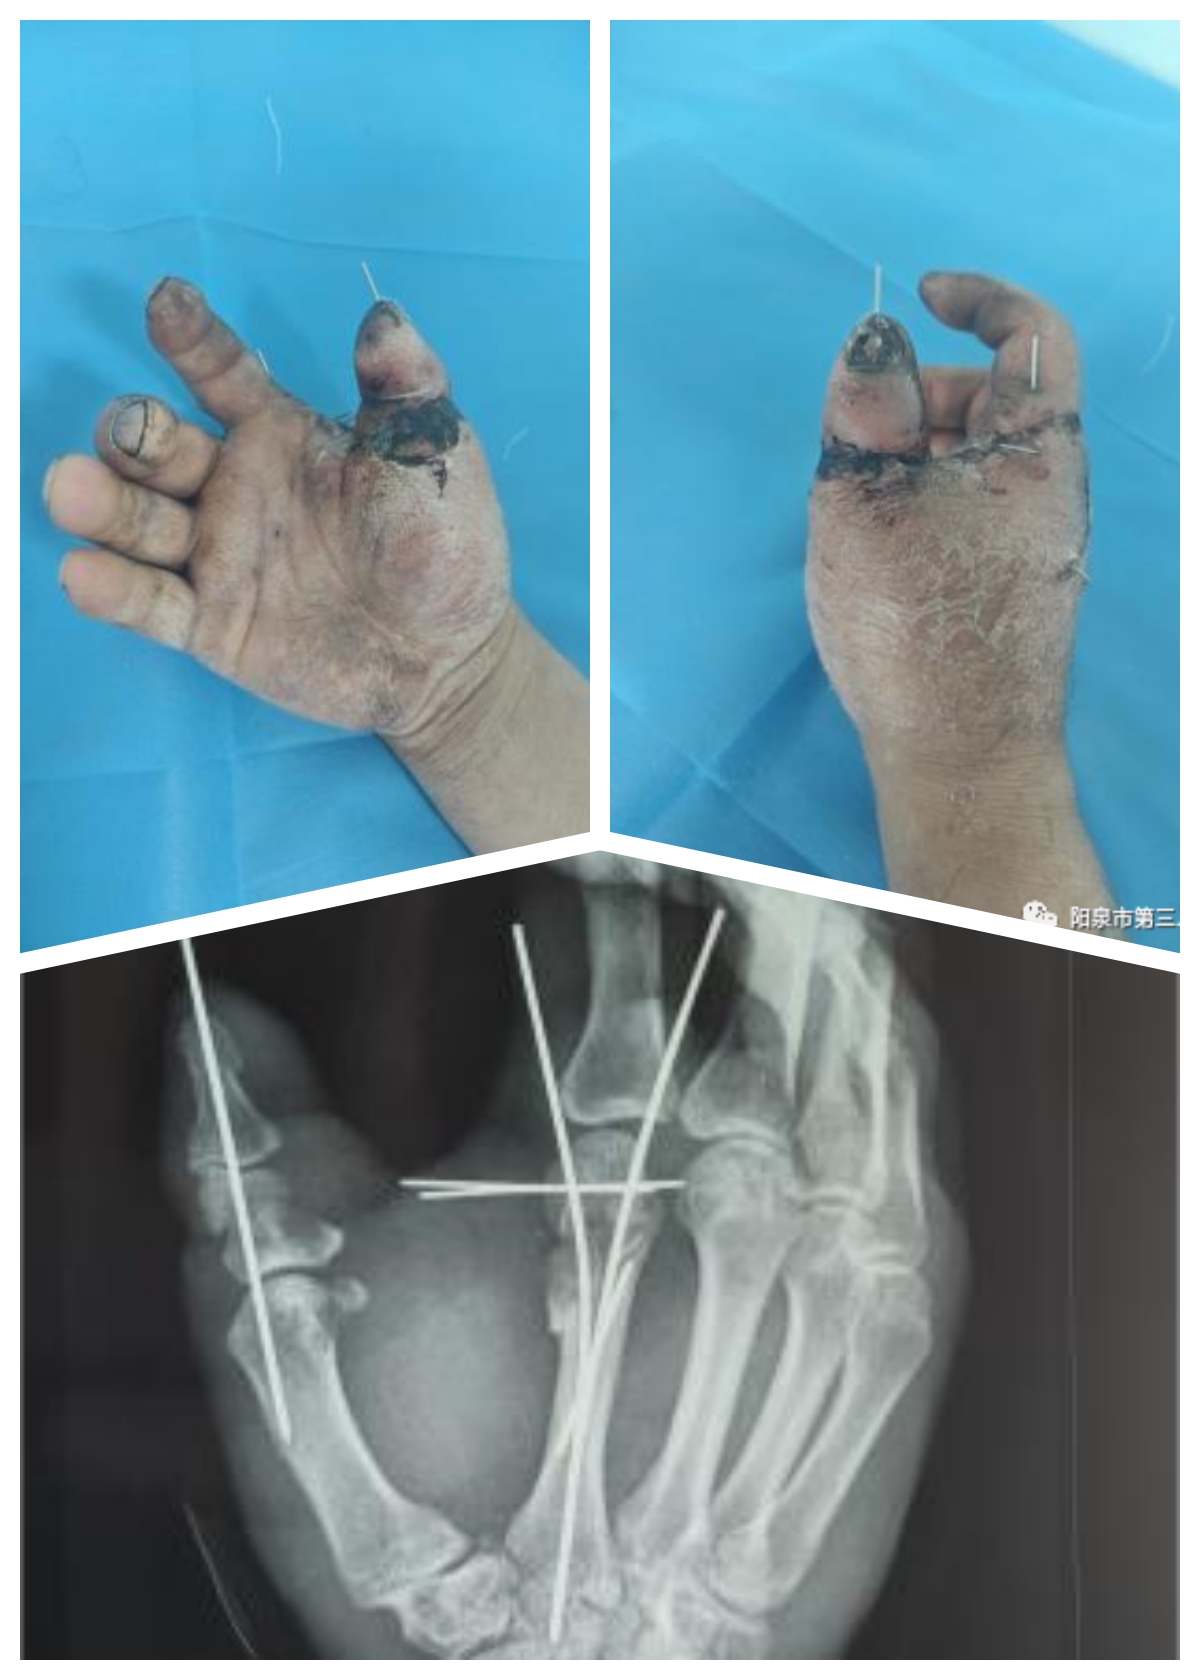

患者,男性,51岁,在单位工作时不慎被石头砸伤右手,致拇指完全离断、第2掌骨粉碎性骨折,紧急到院就诊。值班医师崔爽爽接诊,查看伤情发现,患者右手拇指于近节近端完全离断,仅屈指深肌腱、双侧指神经及桡侧0.5cm表皮相连,离断指体无血运,指体呈苍白色;第2掌骨粉碎性骨折。离断指体的血管、神经已经非常纤细且损伤严重,再植的难度很大。

手外科团队迅速完成术前检查及准备,展开手术。经清创、探查,医生发现,患者离断的拇指近节指骨呈粉碎性,指动脉完全断裂且栓塞,局部软组织挫灭、污染严重。经研判后,团队将患者拇指骨折断端进行短缩修整,使用克氏针固定断指,在显微镜下吻合手指动静脉并修复伸肌腱。手术历时5小时完成。术后,患者再植拇指皮肤色泽红润,血运好。